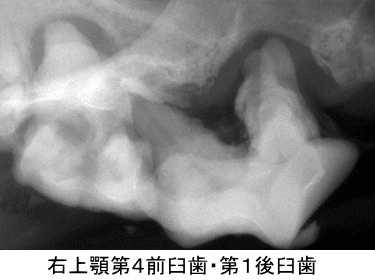

左右上顎第4前臼歯と第1後臼歯です。どの歯もポケットは12mm以上ありました。

第4前臼歯の1根が口腔鼻腔ろうとなっていたため抜歯を決定しました。